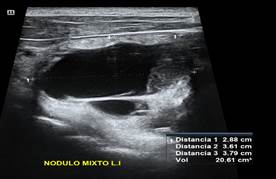

CASO: Paciente masculino de 74 años de edad con antecedentes de hipotiroidismo en tratamiento con levotiroxina de 88mcg al día, a la valoración ecográfica presenta imagen mixta, con vegetaciones hacia polo inferior y tabique transverso hiperecogénico completo con componente quístico 70% (1p) - isoecogénica (1p) - bordes bien definidos - más ancha que alta - no calcificaciones, total 2 puntos (TI-RADS 2) - mide 2.8 x 3.6 x 3.7 cm, volumen 20.61 ml, ligera vascularidad perinodular.

Paciente sometido a inyección percutánea con etanol en donde se evidencia una disminución considerable del volumen nodular, a los 2 meses 5 días se evidencia un volumen 4.08ml con una taza de éxito del 80.21%

Imagen 1. Nódulo mixto pre ablación etanol

Fuente: Elaboración Propia